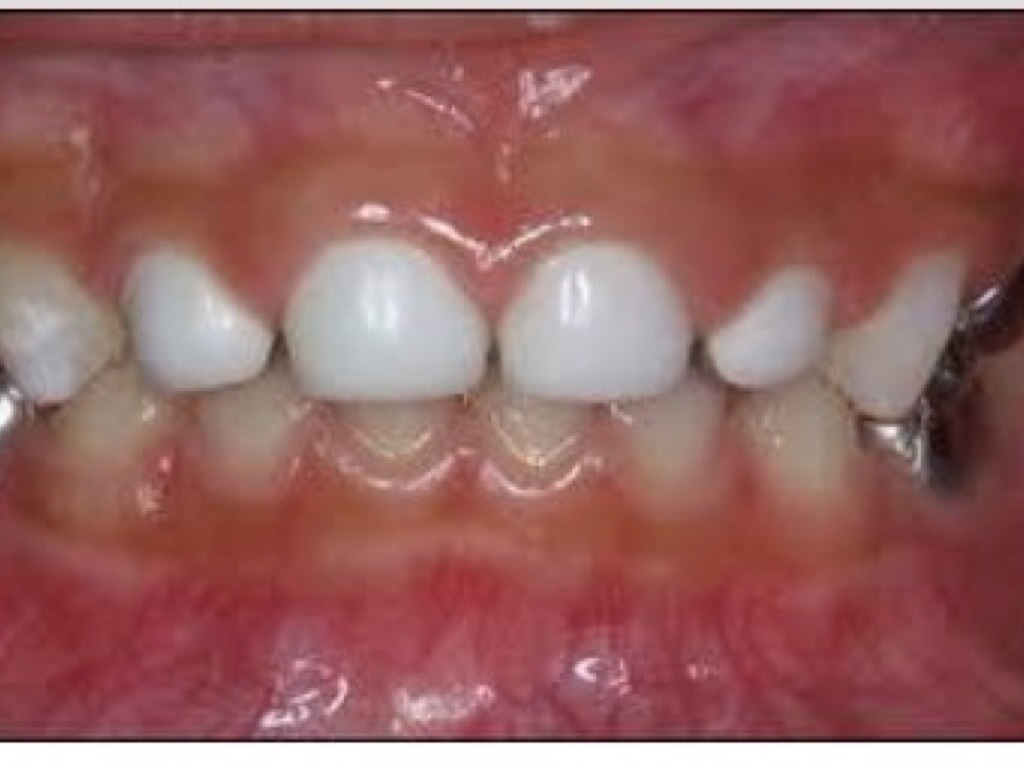

CORONAS

29.

Untitled Slide